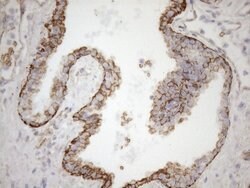

KRT16 Monoclonal Antibody (OTI1G1), TrueMAB™, OriGene

KRT16 is a member of the keratin gene family. The keratins are intermediate filament proteins responsible for the structural integrity of epithelial cells and are subdivided into cytokeratins and hair keratins. Most of the type I cytokeratins consist of acidic proteins which are arranged in pairs of heterotypic keratin chains and are clustered in a region of chromosome 17q12-q21. This keratin has been coexpressed with keratin 14 in a number of epithelial tissues, including esophagus, tongue, and hair follicles. Mutations in this gene are associated with type 1 pachyonychia congenita, non-epidermolytic palmoplantar keratoderma and unilateral palmoplantar verrucous nevus.Specifications

| Immunohistochemistry (Paraffin), Western Blot | |